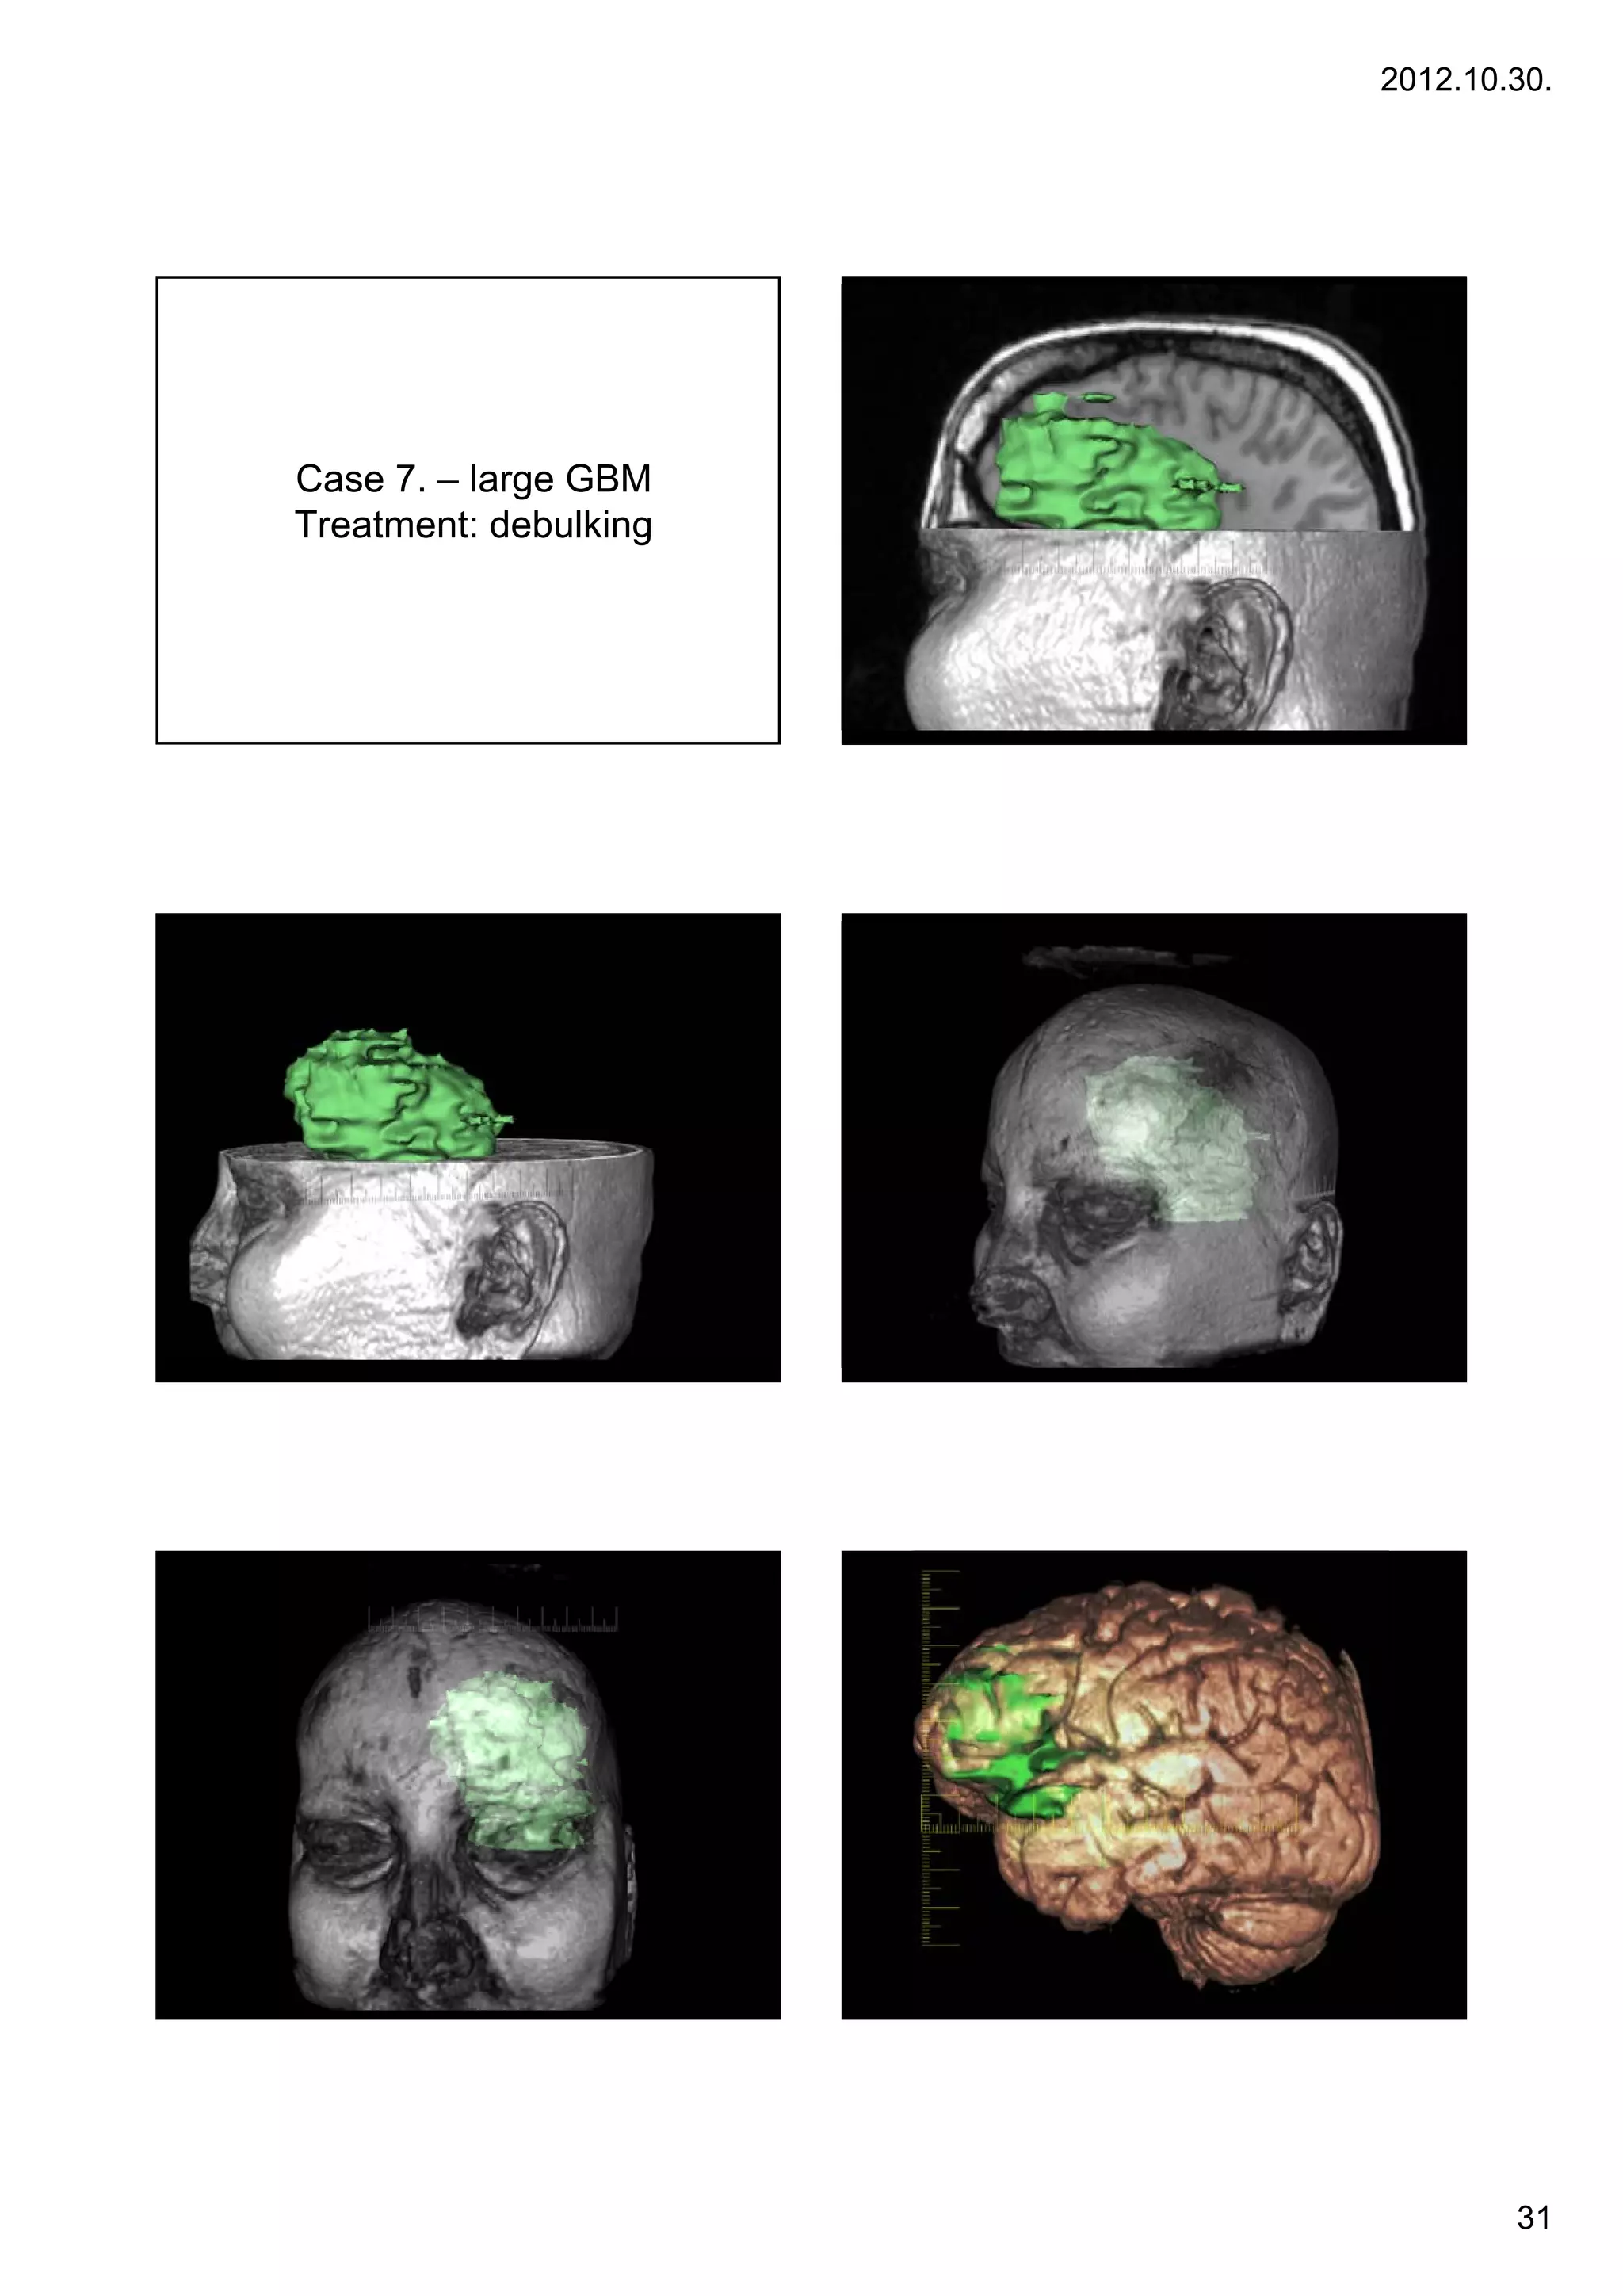

Case 7. – large GBM

Treatment: d b lki

T           debulking

Glioblastoma multiforme

•Glioblastoma multiforme (GBM) is the most common and

most aggressive malignant primary brain tumor in humans,

involving glial cells and accounting for 52% of all functional

tissue brain tumor cases and 20% of all intracranial tumors.

Despite being the most prevalent form of primary brain

Case 3.   tumor, GBM incidence is only 2–3 cases per 100,000

,                       y            p       ,

people in Europe and North America. According to

the WHO classification of the tumors of the central nervous

system, the standard name for this brain tumor is

"glioblastoma"; it presents two variants: giant cell

glioblastoma and gliosarcoma.

•Treatment can involve chemotherapy, radiation,

radiosurgery, corticosteroids, antiangiogenic therapy,

surgery[1] and experimental approaches such as gene

transfer.[2]